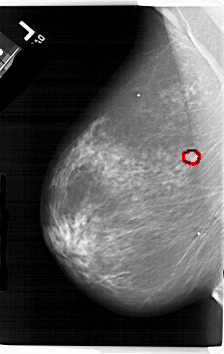

FILE: A_1657_1.LEFT_MLO.OVERLAY

TOTAL_ABNORMALITIES 1

ABNORMALITY 1

LESION_TYPE MASS SHAPE LOBULATED MARGINS OBSCURED

ASSESSMENT 4

SUBTLETY 3

PATHOLOGY MALIGNANT

TOTAL_OUTLINES 1

BOUNDARY